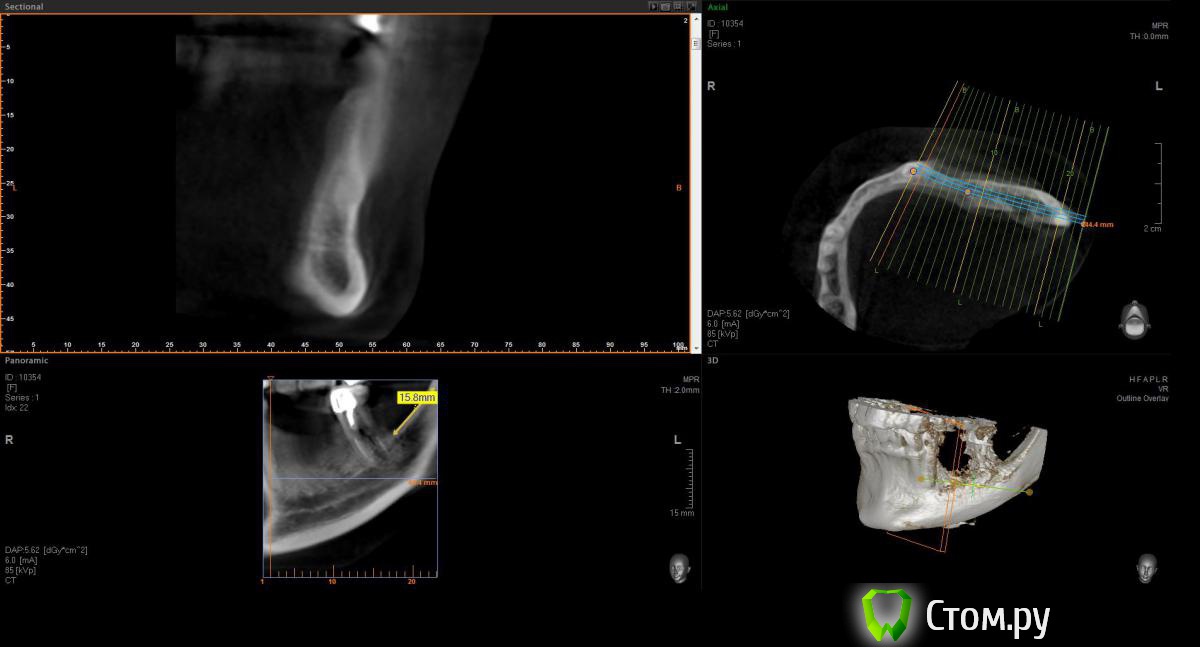

Opimar Опубликовано 21 июня, 2014 Поделиться Опубликовано 21 июня, 2014 Здравствуйте коллеги. Прошу вашей помощи и совета с пациенктой. В анамнезе травматичное удаление около 2-3 лет назад 35-36. Со слов пацинтки удалялось долотом и в 2 приема, вообщем по прошествию времени результат плачевный К мостовидному протезу пациентка не готова, очень хочет лечение с имплантантами и готова к костной пластике. Восстановить такой дефект ,если я правильно понимаю, более-менее прогнозируемо можно только с трансплантацией аутокостных блоков. Как раз по типу того как выкладывал Mane http://forum.stom.ru/topic/25799-kk-monokortikalnye-bloki/ либо по Кюри. Сам склоняюсь к забору блока с наружной косой линии или с подбородка. С блоками работать буду первый раз. Прослушал курсы Томаса Хансера. Прошу высазать идеи и предложения,возможны ли альтернативные методы? Кт прилагаю. Спасибо Ссылка на комментарий

Opimar Опубликовано 21 июня, 2014 Автор Поделиться Опубликовано 21 июня, 2014 Выкладываю еще. Пошагово от 34-37 Ссылка на комментарий

Bier Опубликовано 21 июня, 2014 Поделиться Опубликовано 21 июня, 2014 Выкладываю еще. Пошагово от 34-37темная точка достаточно высоко, это по моему не нерв, нерв ниже, я правильно понимаю? Ссылка на комментарий

Opimar Опубликовано 21 июня, 2014 Автор Поделиться Опубликовано 21 июня, 2014 темная точка достаточно высоко, это по моему не нерв, нерв ниже, я правильно понимаю?Да он ниже и язычнее. Провел от менталиса там еще запас есть. Ссылка на комментарий